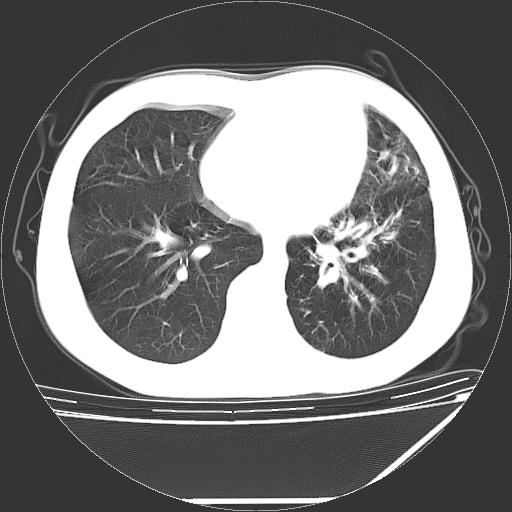

男,13岁,咳嗽、咳痰伴发热一周。

上纵隔课件多枚淋巴结,部分相互融合,左侧支气管壁增厚,肺纹理较右侧增粗,患者,男,13岁,

中上纵隔见多枚淋巴结肿大,部分相互融合成团片,左肺门增大,上叶支气管变窄,肺内多处斑片状 索条状及棉絮状致密影。临床“男,13岁,咳嗽、咳痰伴发热一周。”首先考虑:原发综合征!不除外淋巴瘤可能!

中上纵隔见多枚淋巴结肿大,部分相互融合成团片,左肺门增大,上叶支气管变窄,左肺支气管血管束增粗,可见磨玻璃样影。临床“男,13岁,咳嗽、咳痰伴发热一周。”首先考虑:淋巴瘤可能性大!

中上纵隔见多枚淋巴结肿大,部分相互融合成团片,纵隔内脂肪间隙模糊,左肺门增大,上叶支气管变窄,左肺支气管血管束增粗,可见磨玻璃样影。考虑纵隔淋巴管炎